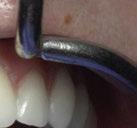

(Figuras 22 y 23). Se realiza fresado transgingival mínimamente invasivo y guiado hasta la inserción de los implantes, siguiendo el protocolo preestablecido e indicado (Figuras 24 a 26).

Durante la colocación de los implantes comprobamos una inserción con torque superior a 35 N/cm2

Retiramos la férula y comprobamos una correcta estabilidad primaria mediante mediación de valores

ISQ favorables en la mayoría de los implantes. Seguidamente se extraen los dientes remanentes que han actuado de medio retentivo para la férula quirúrgica.

Dentro de la fase quirúrgica propiamente dicha, una vez terminada la inserción de los implantes y

comprobada su estabilidad primaria, colocamos pilares transepiteliales

Multiplus para registrar una impresión digital mediante escaneado sobre ellos (Figuras 27 a 29)